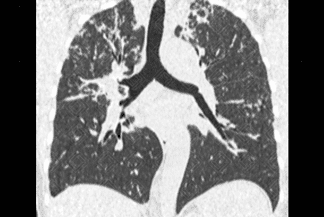

Texto alternativo para a imagem Figuras 1, 2, 3, 4 e 5. Créditos: Dra. Elazir Mota - Rio de Janeiro/RJ

Descrição das figuras 1, 2, 3, 4 e 5: Tomografia computadorizada do tórax com cortes axiais evidenciando pequenos nódulos distribuídos principalmente ao longo dos brônquios e vasos pulmonares (setas vermelhas). Nos cortes coronal e sagital observa-se o predomínio das anormalidades descritas nas regiões superiores e médias, de localização mais central.

• As alterações pulmonares predominam nas regiões centrais e lobos superiores, sendo geralmente bilaterais e simétricas. Predominam os pequenos nódulos sólidos com distribuição perilinfática, ou seja, ao longo dos brônquios, septos interlobulares, vasos pulmonares e regiões subpleurais. Lesões nodulares escavadas e derrame pleural são raros na doença;